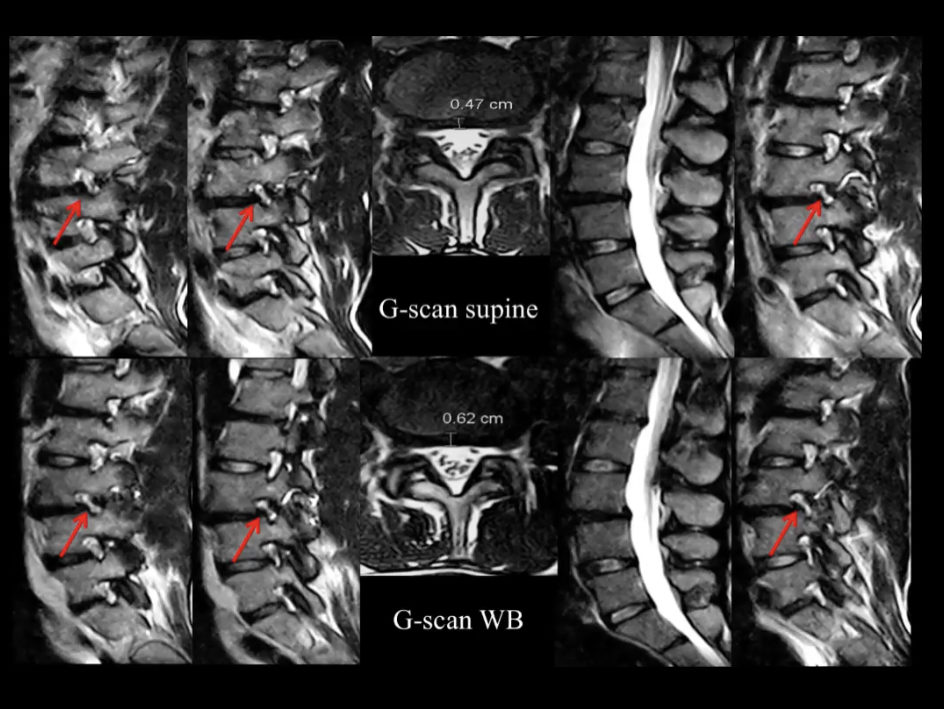

Unique Weight-bearing MRI Capabilities

Weight-bearing studies are easy to perform, allowing patients to be images in the position in which they experience symptoms and providing documentation that can be critical in pre-surgical workflow.

Thanks to a combination of dedicated MSK sequences, advanced RF coils, and patented computing technology, Esaote MRI systems deliver high-quality MSK images in line with today’s throughput constraints.